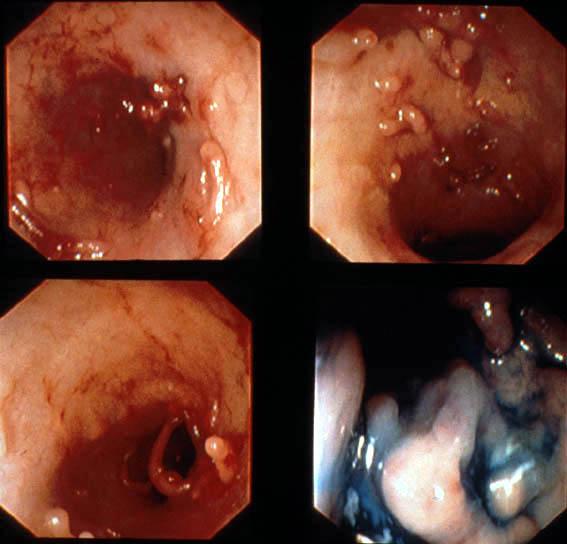

A case of ulcerative colitis showing a progression and remission of diffuse inflammatory polyposis during over a ten-year period.

Tokyo Pref., Cooperative study between National Cancer Center and Kyushu Cancer Center

Inflammatory or ulcerative disease / lesions/Ulcerative colitis

Large intestine(Colon)/Descending colon

Endoscopy